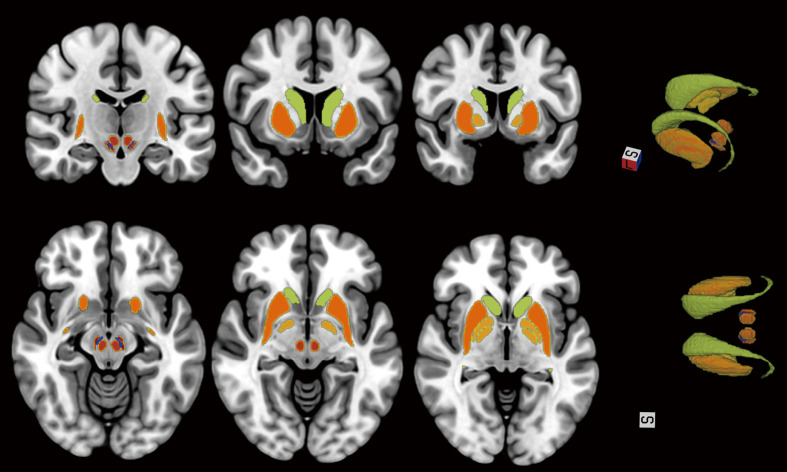

Results: Relative to the HCs, patients with PD demonstrated increased susceptibility values (consistent with higher brain tissue iron deposits) in substantia nigra pars compacta (SNc) and ventral tegmental area (VTA) of the midbrain [Pfalse discovery rate (FDR)<0.05]. Further PD subgroup analysis suggested that compared with HCs, patients with PD-NPA showed increased iron deposition in the right medial superior frontal gyrus (SFGmed), whereas those with PD-PA exhibited more extensive increased iron deposition in SFGmed, extending to bilateral SFGmed [voxel-level P<0.001, cluster-level Pfamily-wise error (FWE)<0.05]. The Apathy Scale (AS) score was positively correlated with the mean susceptibility values of the left SFGmed in the PD-PA group (r=0.651, P=0.001). In the PD-PA group, voxel-wise whole-brain correlation analysis found a positive correlation between the AS score and the susceptibility values in the left SFGmed, left anterior cingulate cortex (ACC), right thalamus, as well as the right superior temporal gyrus (STG) (voxel-level P<0.001, cluster-level PFWE<0.05).

Conclusions: In patients with PD-PA, brain regions associated with brain iron deposition were mainly located in the "mesocorticolimbic loop" (SFGmed and ACC), as well as the STG and thalamus. The present study suggested that abnormal iron deposition in these core brain regions may be associated with abnormal top-down and bottom-up neuroregulation and involved in the mechanism of PD apathy. The present study provides new insights into the pathophysiologic mechanism of PD-PA.